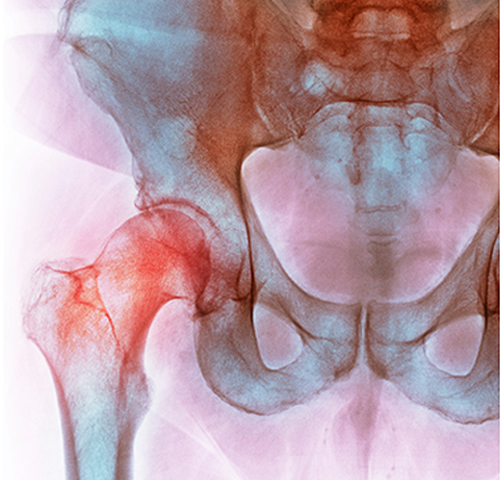

고관절충돌증후군

접히거나 안쪽으로 움직이는 회전운동을 할 때 대퇴골의 경부와 비구 사이

충돌이 일어나는것

으로 대퇴비구 충돌 증후군이라고도 합니다.